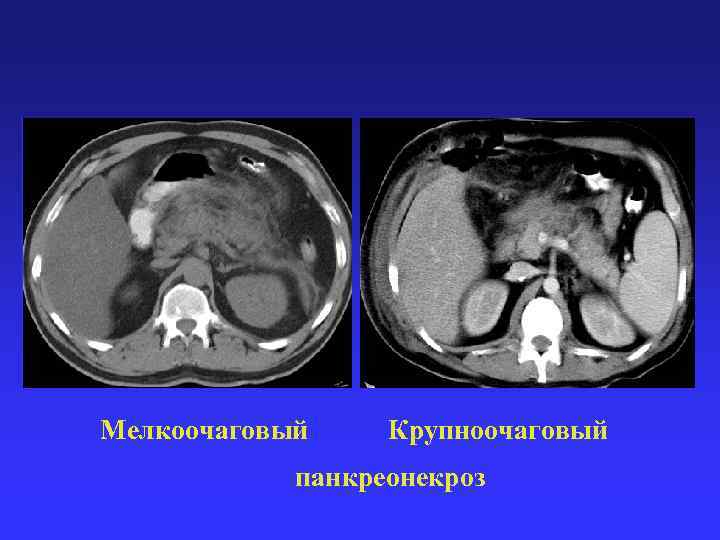

Мелкоочаговый Крупноочаговый панкреонекроз Мелкоочаговый Крупноочаговый панкреонекроз